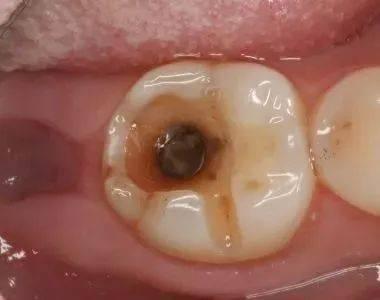

齲齒,通常被稱為蛀牙,是由于細(xì)菌產(chǎn)生的酸性物質(zhì)逐漸侵蝕牙齒硬組織(牙釉質(zhì)、牙本質(zhì))而導(dǎo)致的。當(dāng)口腔中的細(xì)菌與食物殘?jiān)旌闲纬裳谰?,附著在牙齒表面,它們會分解食物中的糖分產(chǎn)生酸。這些酸會溶解牙釉質(zhì)中的礦物質(zhì),逐漸形成齲洞。

(三)齲齒不會自行消失

在絕大多數(shù)情況下,齲齒一旦形成,如果不進(jìn)行干預(yù)治療,齲洞會逐漸擴(kuò)大、加深,進(jìn)而侵犯牙髓,導(dǎo)致牙髓炎、根尖周炎等嚴(yán)重并發(fā)癥。有研究表明,未經(jīng)治療的齲齒在6個(gè)月內(nèi)齲洞深度平均增加約0.5毫米。